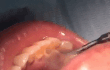

스케일링 해야하는 이유ㄷㄷㄷ